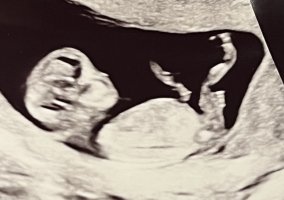

Her kan man legge ut bilder fra tidlig ultralyd og gjette hverandres kjønn.

Nub er hva man kaller barnets kjønnsorgan. Man kan se forskjell på hvilken vinkel den står i. Jenter har gjerne lang flat nub som går rett frem. Gutter har nub som står mer opp og har også ofte det man kaller "stacking". Ser ut som en ball oppå nub.

Bildene må være fra uke 12 og utover. Barnet bør ligge i sideprofil. Husk å skrive hvilken uke+dag bildet er tatt.

Nub teorien er hva ultralydteknikere også vurderer kjønn på før man kan se pung og kjønnslepper. Så har man et godt bilde så vil man kunne se kjønn lenge før oul.